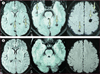

Methods: In this double-blind, placebo-controlled, phase 3 trial, patients with viable intraparenchymal neurocysticercosis were randomly assigned to receive 10 days of combined albendazole (15 mg/kg per day) plus praziquantel (50 mg/kg per day), standard albendazole (15 mg/kg per day), or increased dose albendazole (22·5 mg/kg per day). Randomisation was done with a computer generated schedule balanced within four strata based on number of cysts and concomitant antiepileptic drug. Patients and investigators were masked to group assignment. The primary outcome was complete cyst resolution on 6-month MRI. Enrolment was stopped after interim analysis because of parasiticidal superiority of one treatment group. Analysis excluded patients lost to follow-up before the 6-month MRI. This trial is registered with ClinicalTrials.gov, number NCT00441285.

Findings: Between March 3, 2010 and Nov 14, 2011, 124 patients were randomly assigned to study groups (41 to receive combined albendazole plus praziquantel [39 analysed], 43 standard albendazole [41 analysed], and 40 increased albendazole [38 analysed]). 25 (64%) of 39 patients in the combined treatment group had complete resolution of brain cysts compared with 15 (37%) of 41 patients in the standard albendazole group (rate ratio [RR] 1·75, 95% CI 1·10-2·79, p=0·014). 20 (53%) of 38 patients in the increased albendazole group had complete cyst resolution at 6-month MRI compared with 15 (37%) of 41 patients in the standard albendazole group (RR 1·44, 95% CI 0·87-2·38, p=0·151). No significant differences in adverse events were reported between treatment groups (18 in combined treatment group, 11 in standard albendazole group, and 19 in increased albendazole group).